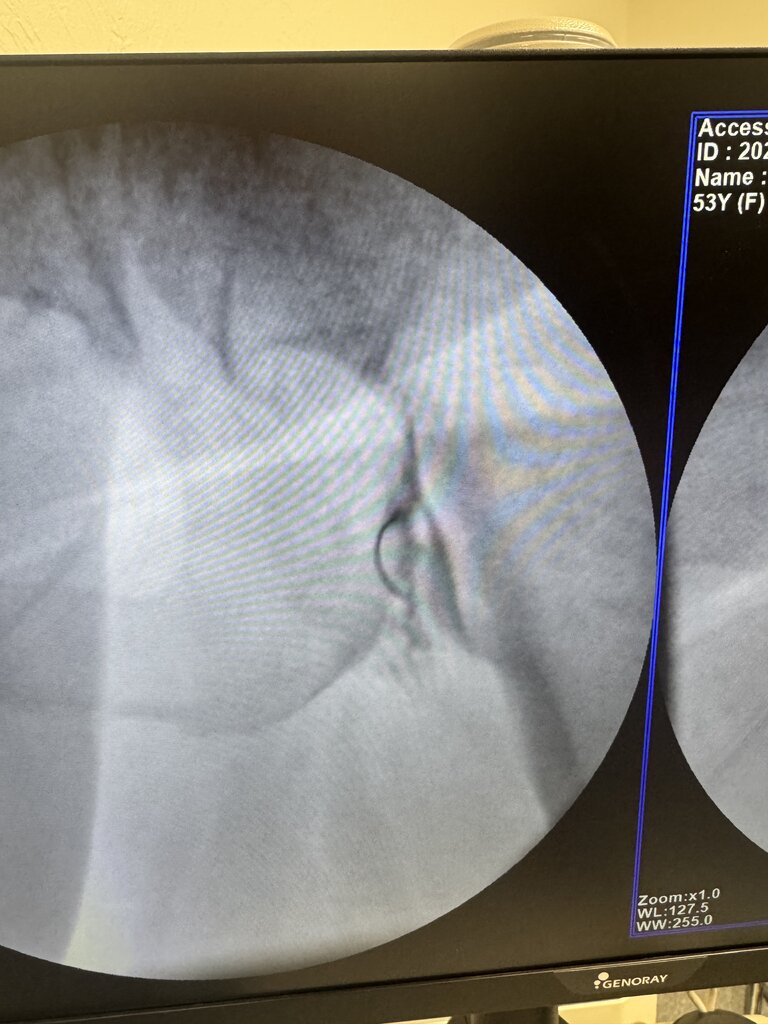

Yeah super easy. Prone AP. CLO until ischial tuberosity and lesser troch are kissing. Touch down on lateral border of ischial tuberosity, walk off to touch down on troch, pull back half the distance and you'll be in belly of muscle. If you look at axial cut of MRI you'll see what I mean.

I took the opposite approach as above as when I reviewed the anatomy on MRI sciatic and vasculature was closer to ischial tuberosity than trochanter and there was more muscle belly that overlies the lesser trochanter.

Prone, slight ipsilateral oblique to line up trajectory closer to edge of lesser tuberosity. Touch done on os, back up a few mm and inject. Slightly deep but easy injection. 100% local relief with just 1 ml of 2% lido on 2/2 patients I’ve done it on

Went great. Orthopedist was very happy with the contrast spread.